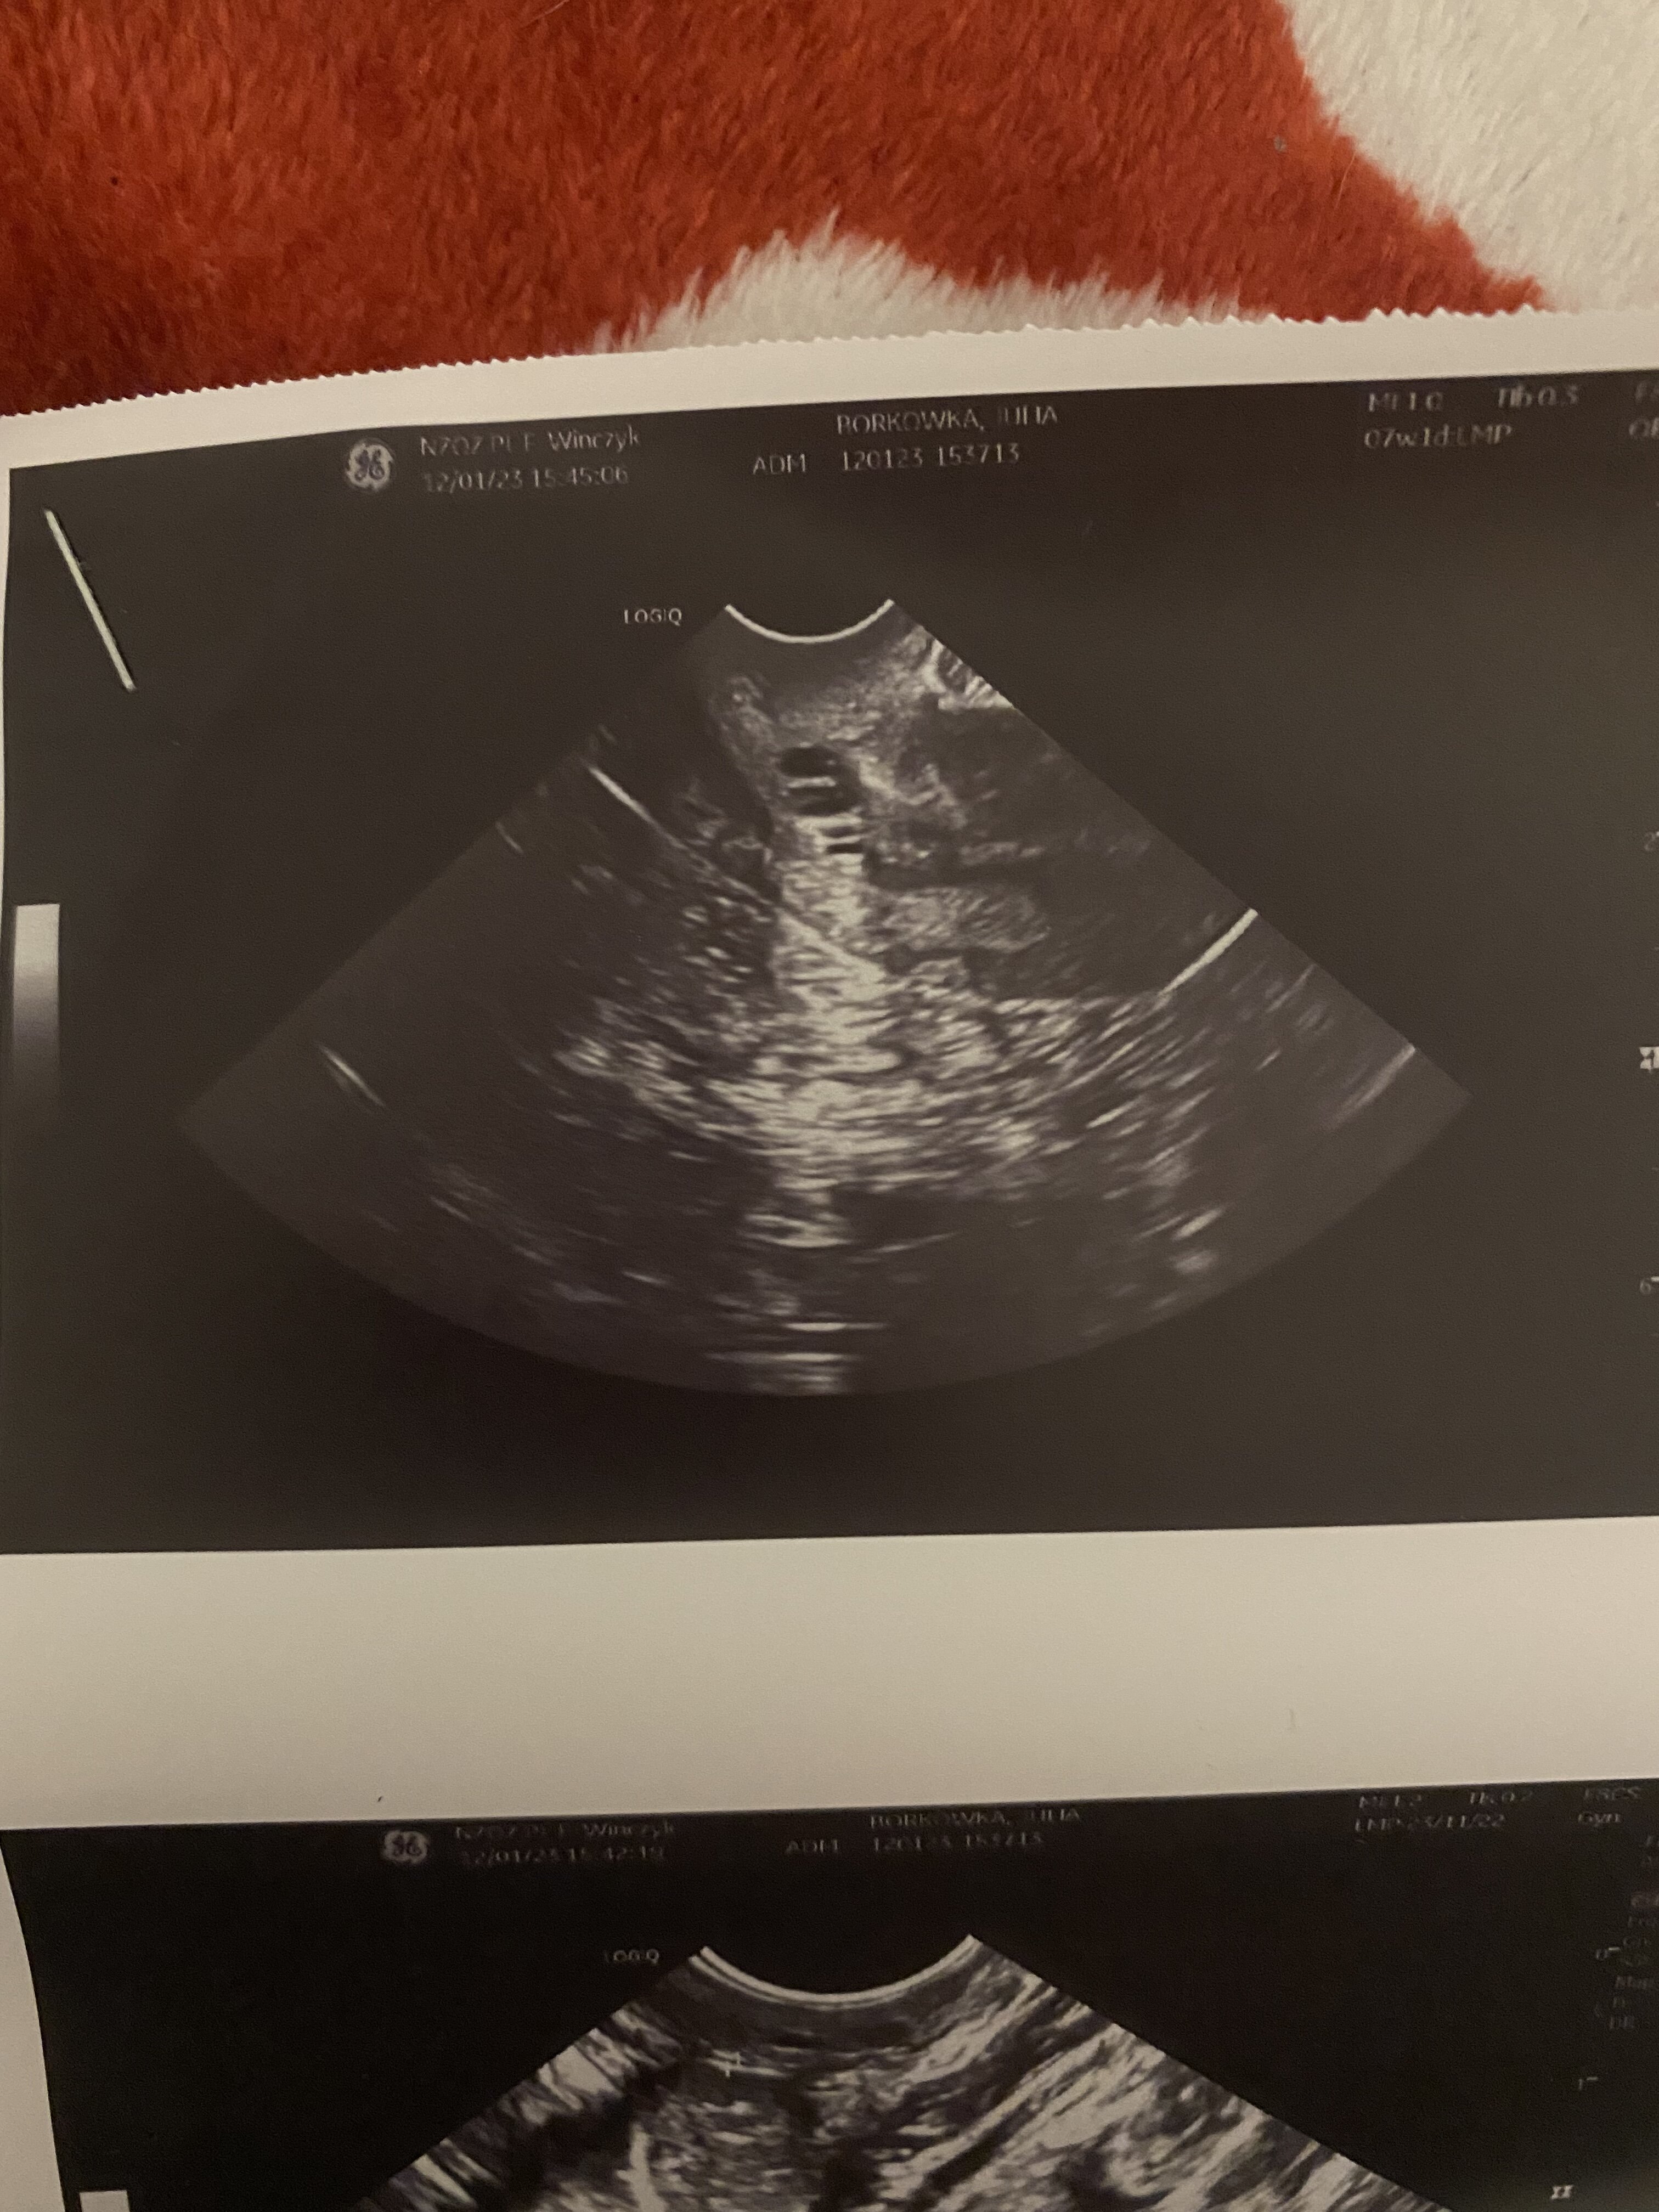

Hej czy to może być ciąża spóźnia mi się okres już 3 tygodnie robiłam test wyszedł negatywny byłam u ginekolog i pani stwierdziła że ciąża może mieć 7 tyg i 1 dzień mówiła że pęcherzyk się rozwija po złej stronie i może to być ciąża pozamaciczna albo poronienie wtórne też mówiła że to ciąża bliźniacza bo jakby dwa pęcherzyki były sama już nie wiem co mam myśleć przepisała mi duphaston na wywołanie miesiączki. Przesyłam zdjęcia usg.